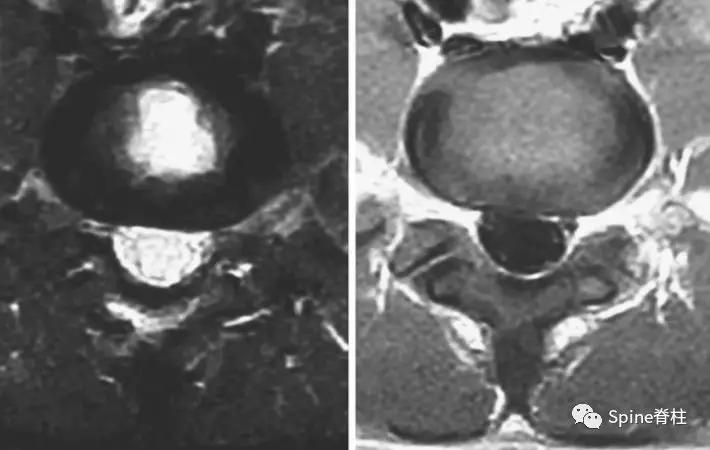

图:箭头所指为离断的椎体后缘

CT是诊断最有效的检查手段

图:A 型为分离部分含皮质骨,不伴椎体后方骨缺损(图A);B 型为分离部分较大,含皮质骨和松质骨,伴椎体后方较大骨缺损(图B);C 型为分离部分较小,含皮质骨和松质骨,伴椎体后方较小骨缺损(图C)。

由于对 腰椎椎体后缘离断症 (陈仲强)发生机理认识各异,有学者认为与青少年骺环未闭及运动创伤导致的椎体及骺环应力较大有关,也有学者认为是一种骨坏死,故命名尚未统一。

PARS 因与单纯 LDH 或 LSS 表现相似,临床易误诊或漏诊,并且 由于骨性致压因素的影响,PARS 患者的症状较单纯 LDH 严重 。对于经保守治疗无效,且存在神经根性症状或马尾神经损伤表现患者,应尽早手术治疗。